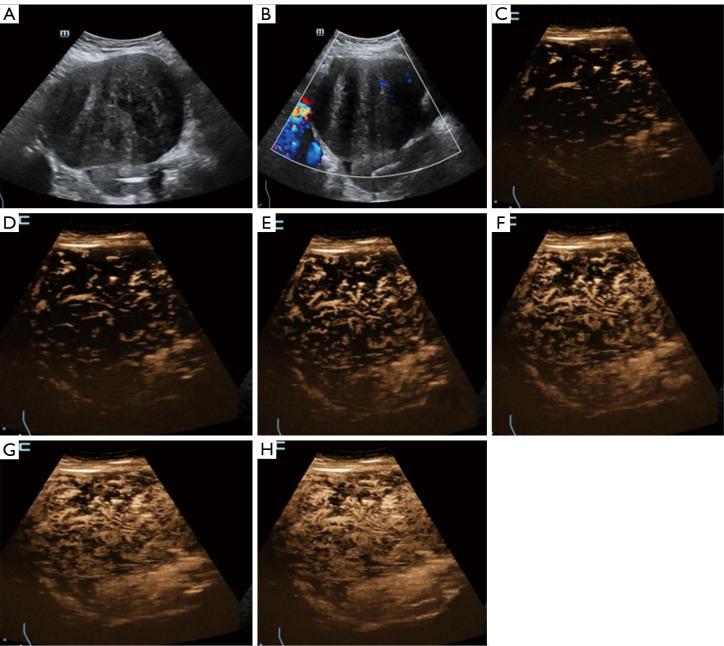

卵巢纤维瘤-卵泡膜细胞瘤组的传统超声及高帧率超声造影特征

Conventional ultrasound and high-frame-rate contrast-enhanced ultrasound characteristics of ovarian thecoma-fibroma groups.

Among the 35 OTFGs, 77.1% tumors (27/35) showed hypoechogenicity in solid parts, with granular or linear hyperechogenicity. All tumors with recorded color Doppler signals (27/27) had no-to-sparse vascularization (color score 1-2). HiFR-CEUS showed typical linear perfusion in the OTFG tumors; 94.3% tumors (33/35) showed hypoenhancement at the peak intensity, as compared to the surrounding myometrium. Seven patients (7/35, 20.0%) had cystic lesions with no internal enhancement. The combination of conventional US and HiFR-CEUS showed the highest diagnostic efficacy for diagnosing OTFGs [sensitivity: 97%, specificity: 100%, accuracy: 99%, PPV: 100%, NPV: 97%, area under the curve (AUC): 0.99] as compared to conventional US (sensitivity: 23%, specificity: 100%, accuracy: 60%, PPV: 100%, NPV: 55%, AUC: 0.61) and HiFR-CEUS (sensitivity: 94%, specificity: 97%, accuracy: 96%, PPV: 97%, NPV: 94%, AUC: 0.96).

35例OTFGs中,77.1%(27/35)的肿瘤实性部分呈低回声,伴有颗粒状或线状高回声。所有记录到彩色多普勒信号的肿瘤(27/27)均无至稀疏血管化(彩色评分1-2)。HiFR-CEUS显示OTFGs肿瘤典型的线状灌注;94.3%(33/35)的肿瘤在峰值强度时呈低增强,与周围肌层相比。7例患者(7/35,20.0%)有囊性病变,内部无增强。与常规超声(灵敏度:23%,特异度:100%,准确度:60%,PPV:100%,NPV:55%,曲线下面积(AUC):0.61)和HiFR-CEUS(灵敏度:94%,特异度:97%,准确度:96%PPV:97%,NPV:94%,AUC:0.96)相比,常规超声与HiFR-CEUS联合应用对OTFGs的诊断效能最高(灵敏度:97%,特异度:100%,准确度:99%,PPV:100%,NPV:97%,AUC:0.99)。